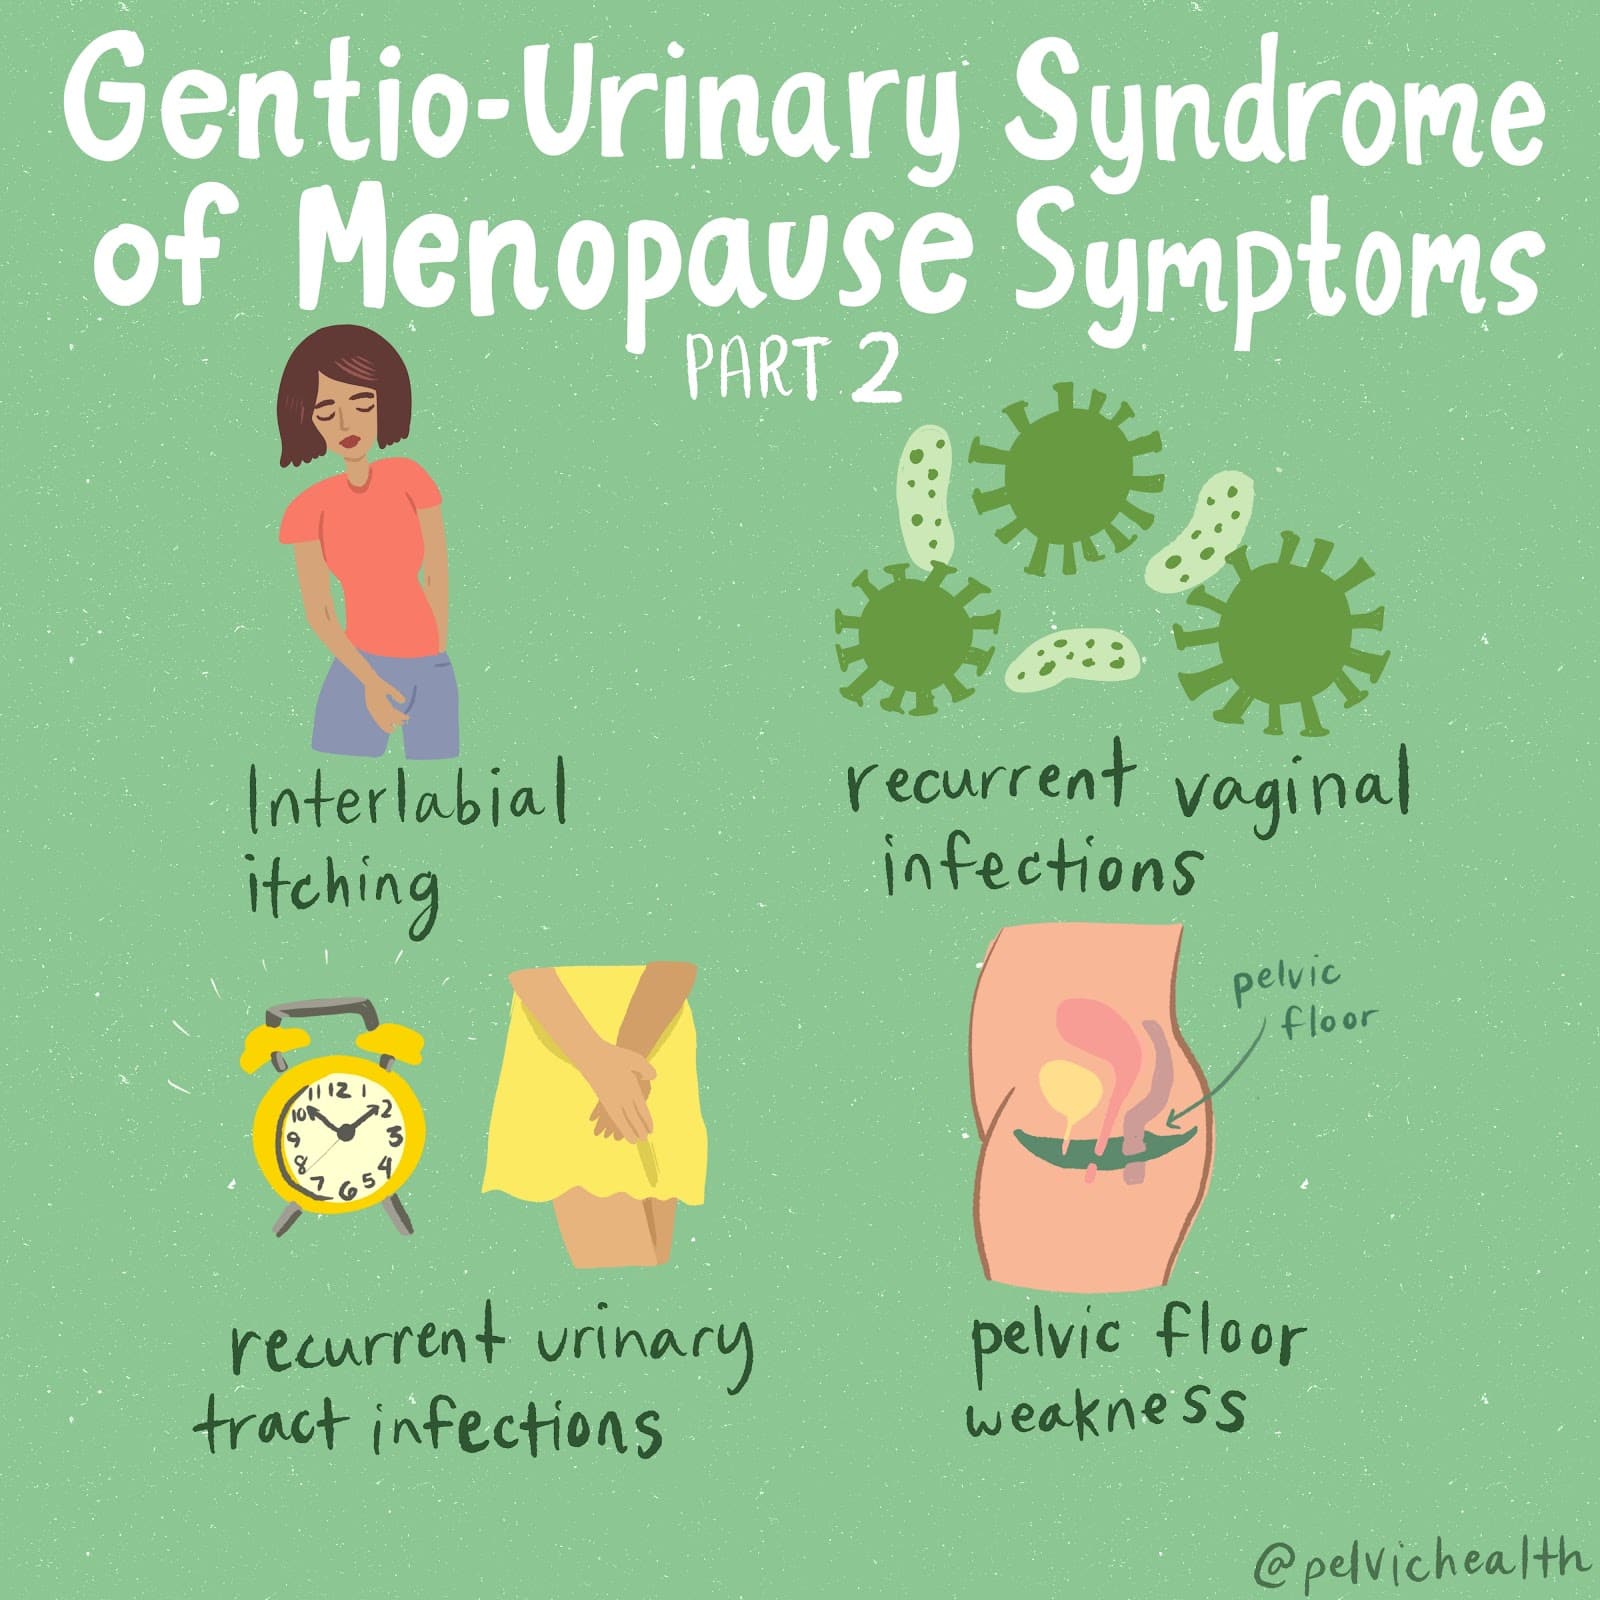

Hormone insufficiency can result in interlabial and vaginal itching. Other dermatologic issues such as Lichen Sclerosus and cutaneous yeast infections are just two of the many factors to also be considered.

Unfortunately people are vulnerable to recurrent vaginal and urinary tract infections in menopause due to:

- pH and tissue changes

- incomplete bladder emptying

- pelvic organ prolapse compromising urinary function

Recurrent infections are a leading cause of pelvic floor dysfunction! They must be stopped or the noxious visceral-somatic input can cause further pain and dysfunction after the infection is cleared. Furthermore, if the infections are left untreated without hormone therapy infections continue to occur and the consequences can be severe. Women can develop unprovoked pain, sex may be impossible, and undetected UTIs can lead to kidney problems and more sinister issues.